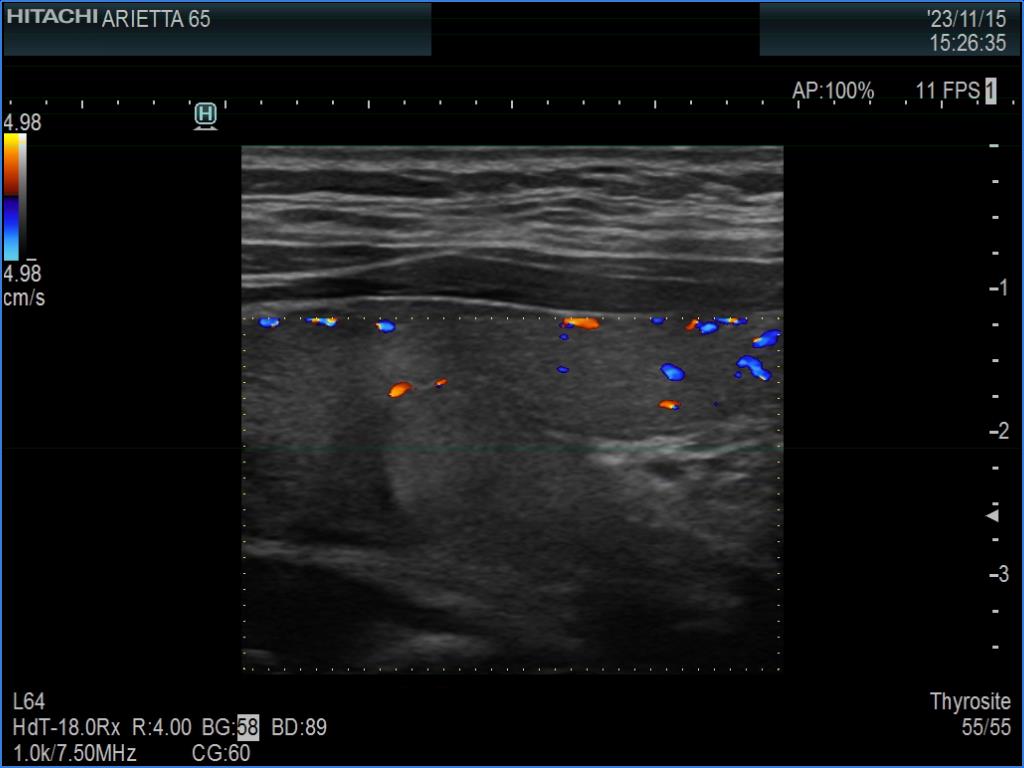

Left lobe, transverse scan, color Doppler mode. The vascularity is not specific.